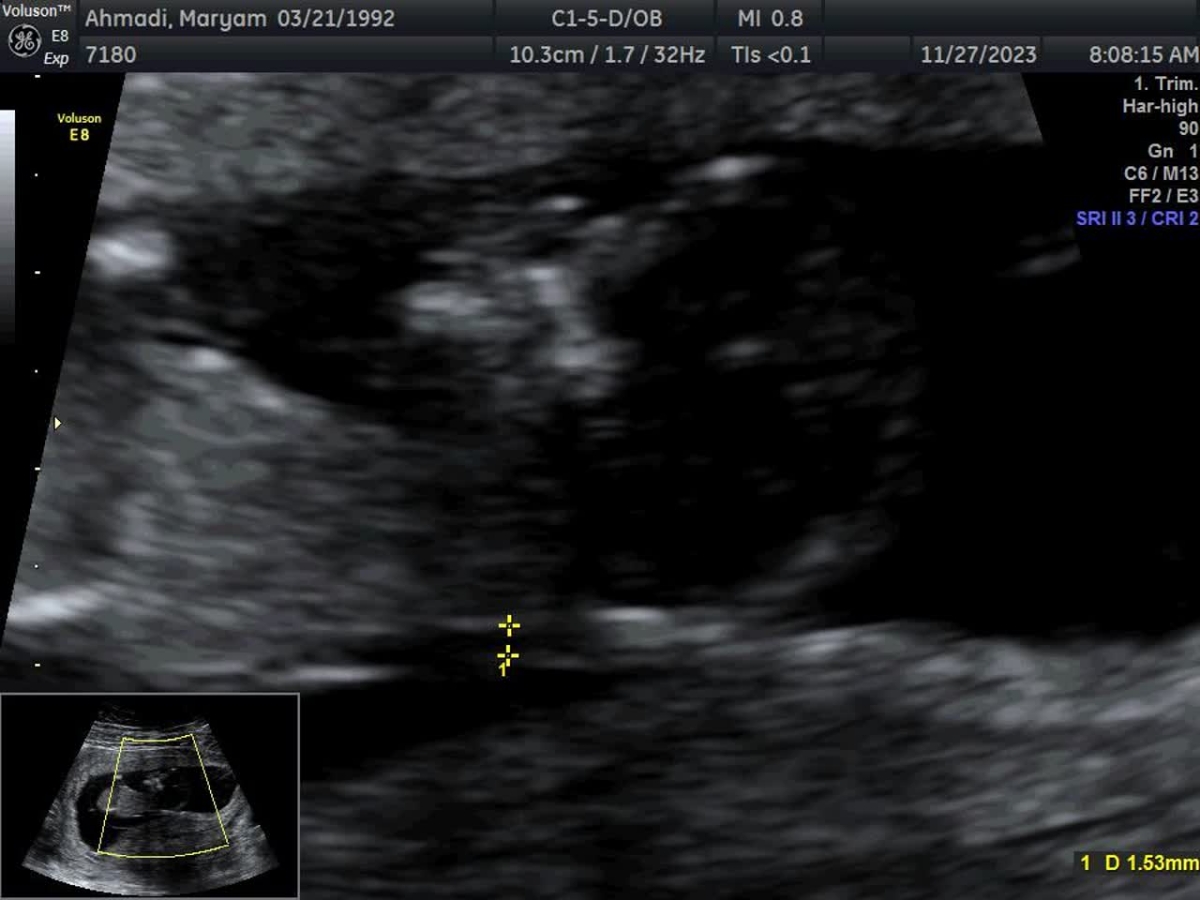

پرسش (1402/09/06):

متخصصین تعیین جنسیت لطفا بیاید 😎

ب نام خدا دختر🫠🫠

ب نظر من شبیه دختراس

پسر

اینم انگار دختره

دختر

ن شبیه نیس این ب نطر من پسره

شبیه دختره